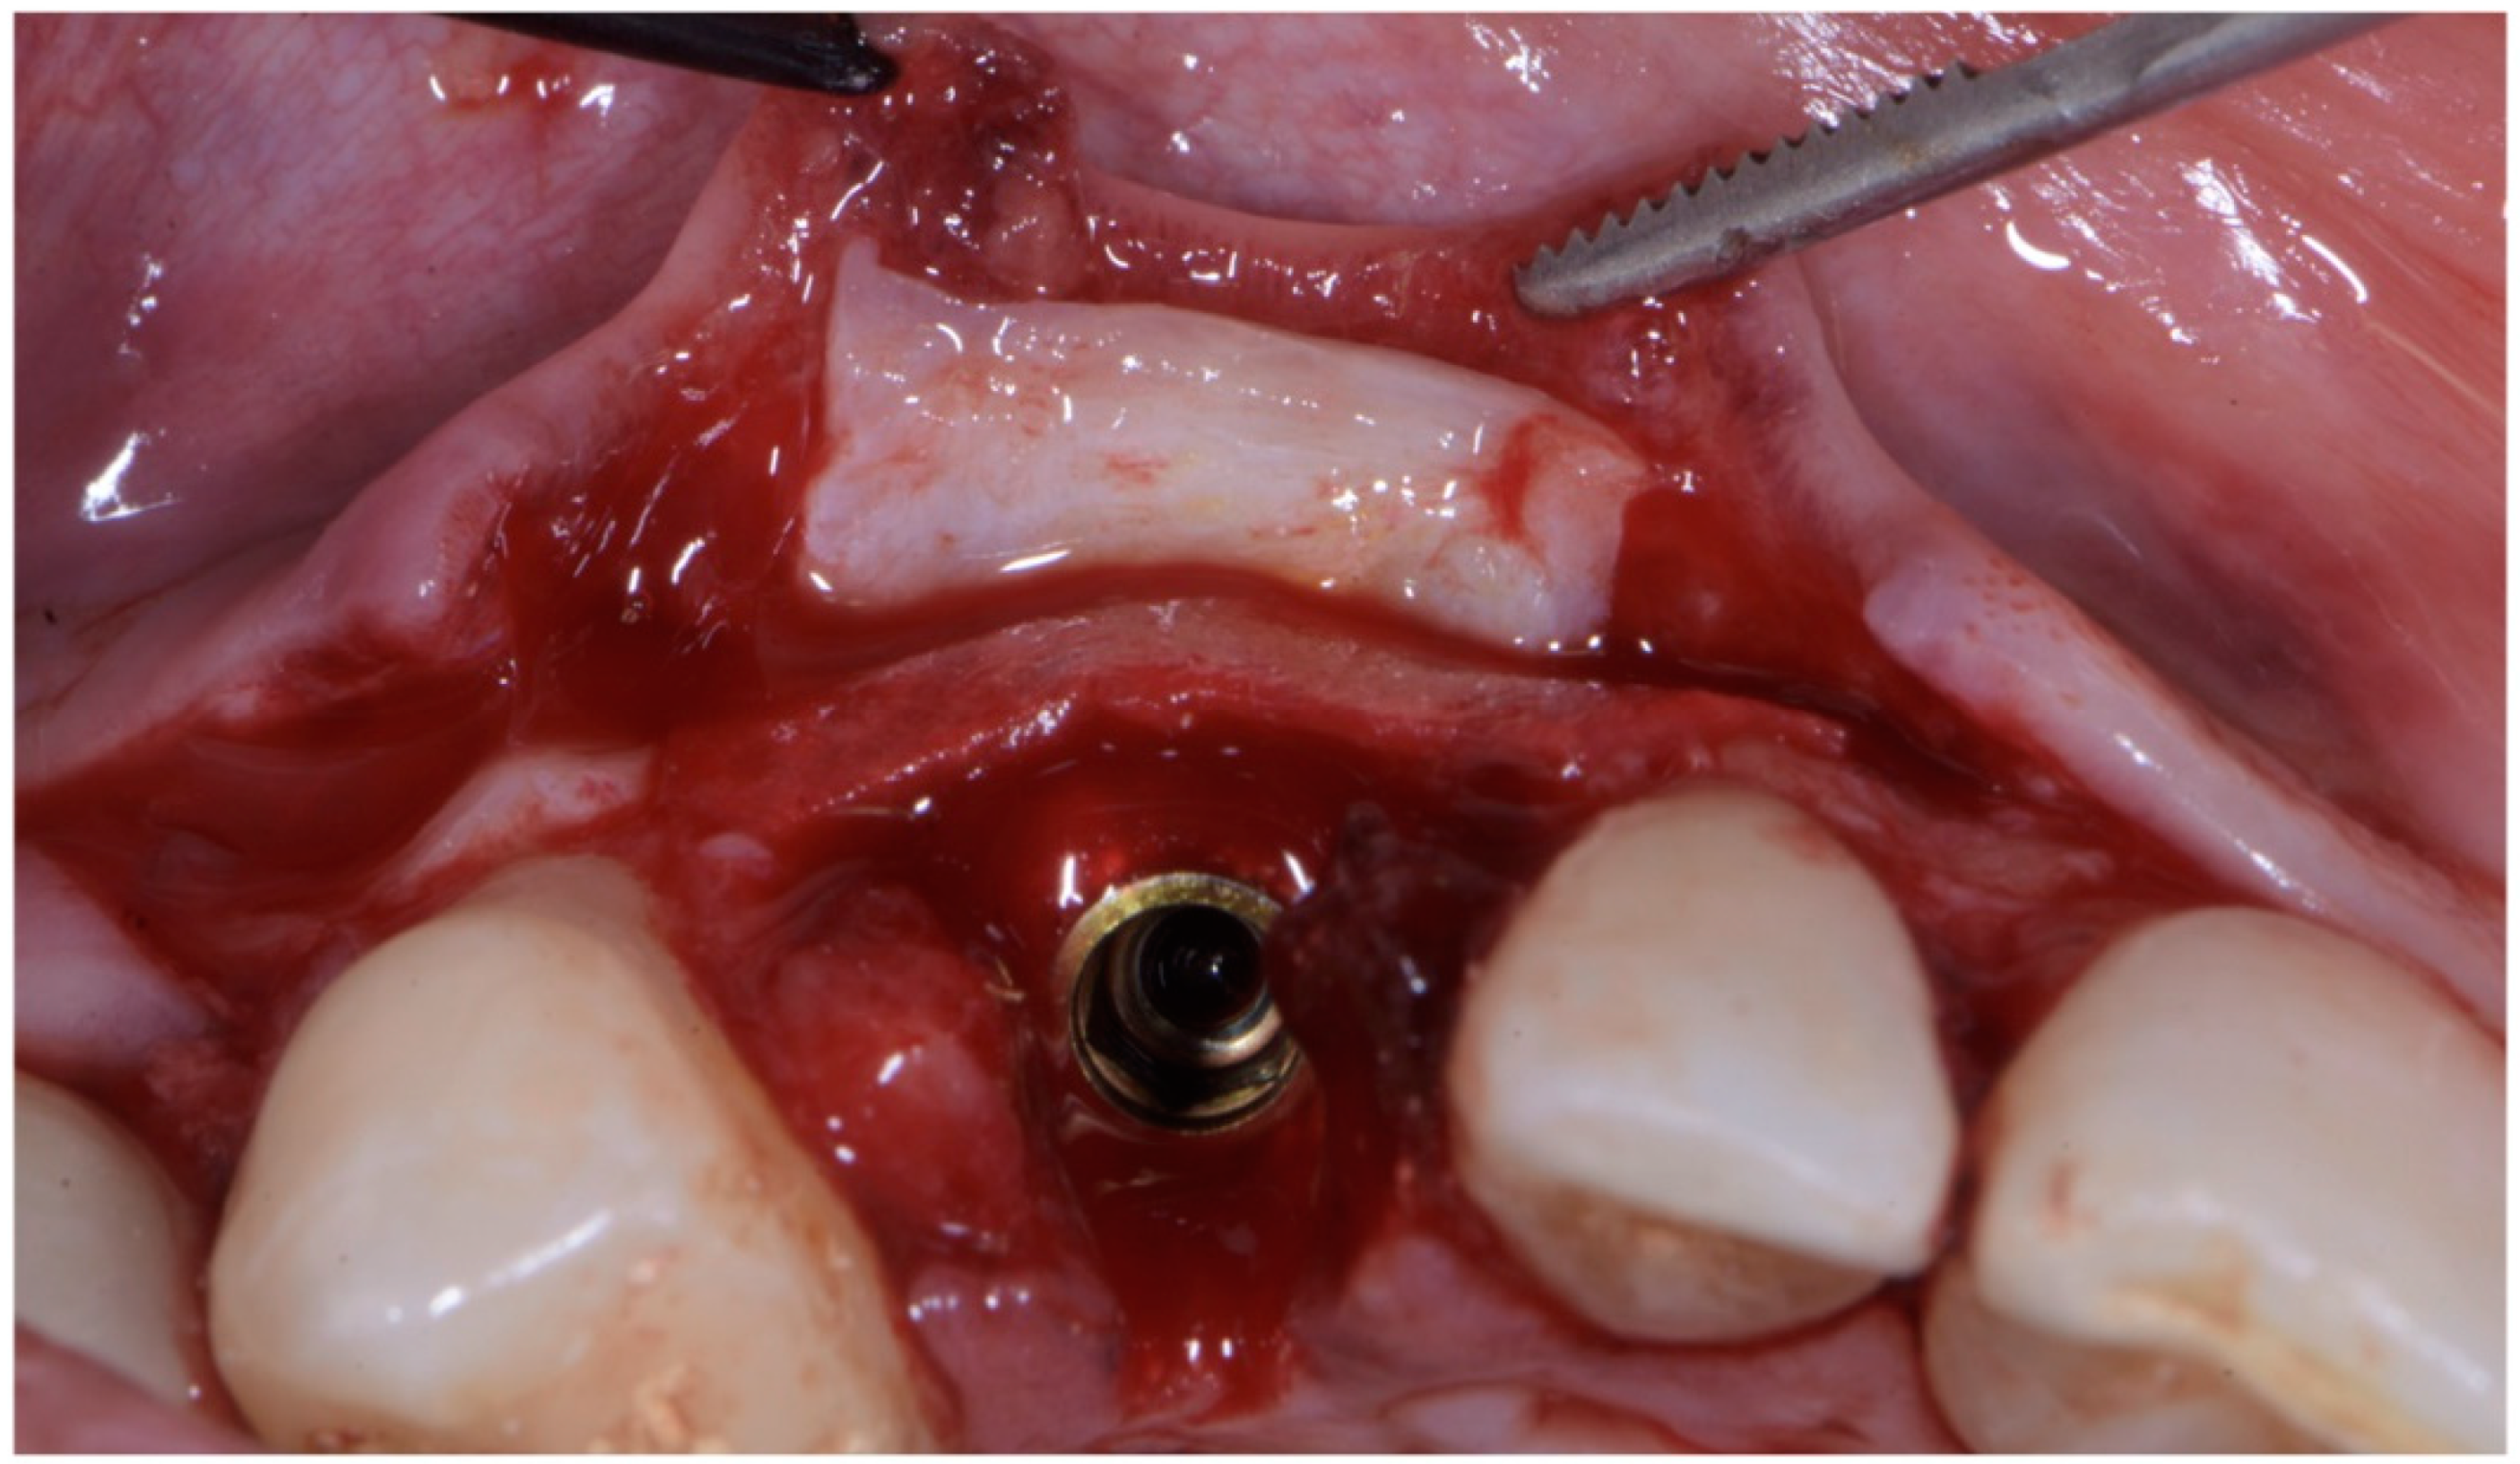

As already evaluated during software planning, after implant insertion, a buccal bone dehiscence of 2 mm occurred. The remaining buccal bone thickness was less than 1 mm. A mixture of biomaterial (Cerabone; Botiss) and autologous bone was placed to cover the exposed implant threads and the thin layer of remaining buccal bone and to fill the gap between the implant surface and the socket wall (Figure 7). Bone filler material should be limited to the rough implant surface, extending as little as possible to the transmucosal collar; however, the biomaterial positioning should be slightly in excess to avoid the loss of biomaterial during the following phase. If there is still an excess, it should be removed just before the very last suture. The biomaterial was then stabilized using a thin pericardium membrane (Jason Membrane; Botiss) placed between the bone particles and a connective-tissue graft (Figure 8a,b). The pericardium membrane was sutured to the periosteum left appositively laterally to the membrane.

Figure 7. Biomaterial and autologous bone placed to cover the exposed implant threads and to fill the gap between implant surface and socket wall.